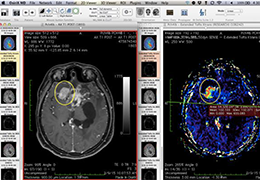

ART-Plan™ Artificial Intelligence Contouring